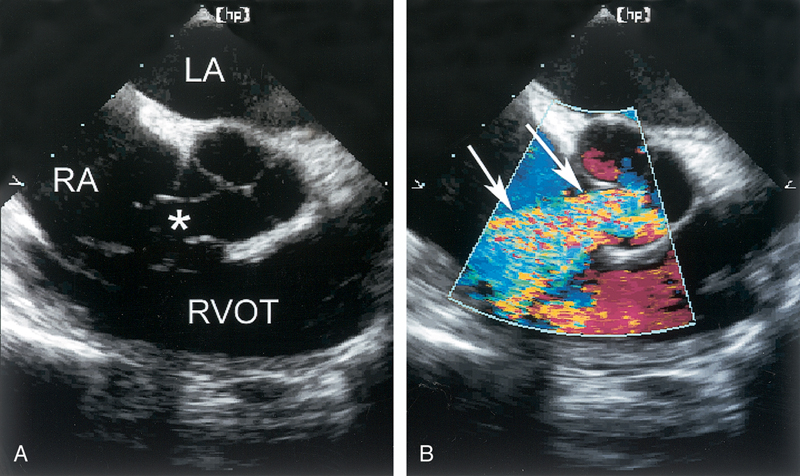

فحوصات تشخيصية لبعض امراض القلب والشرايين التاجية